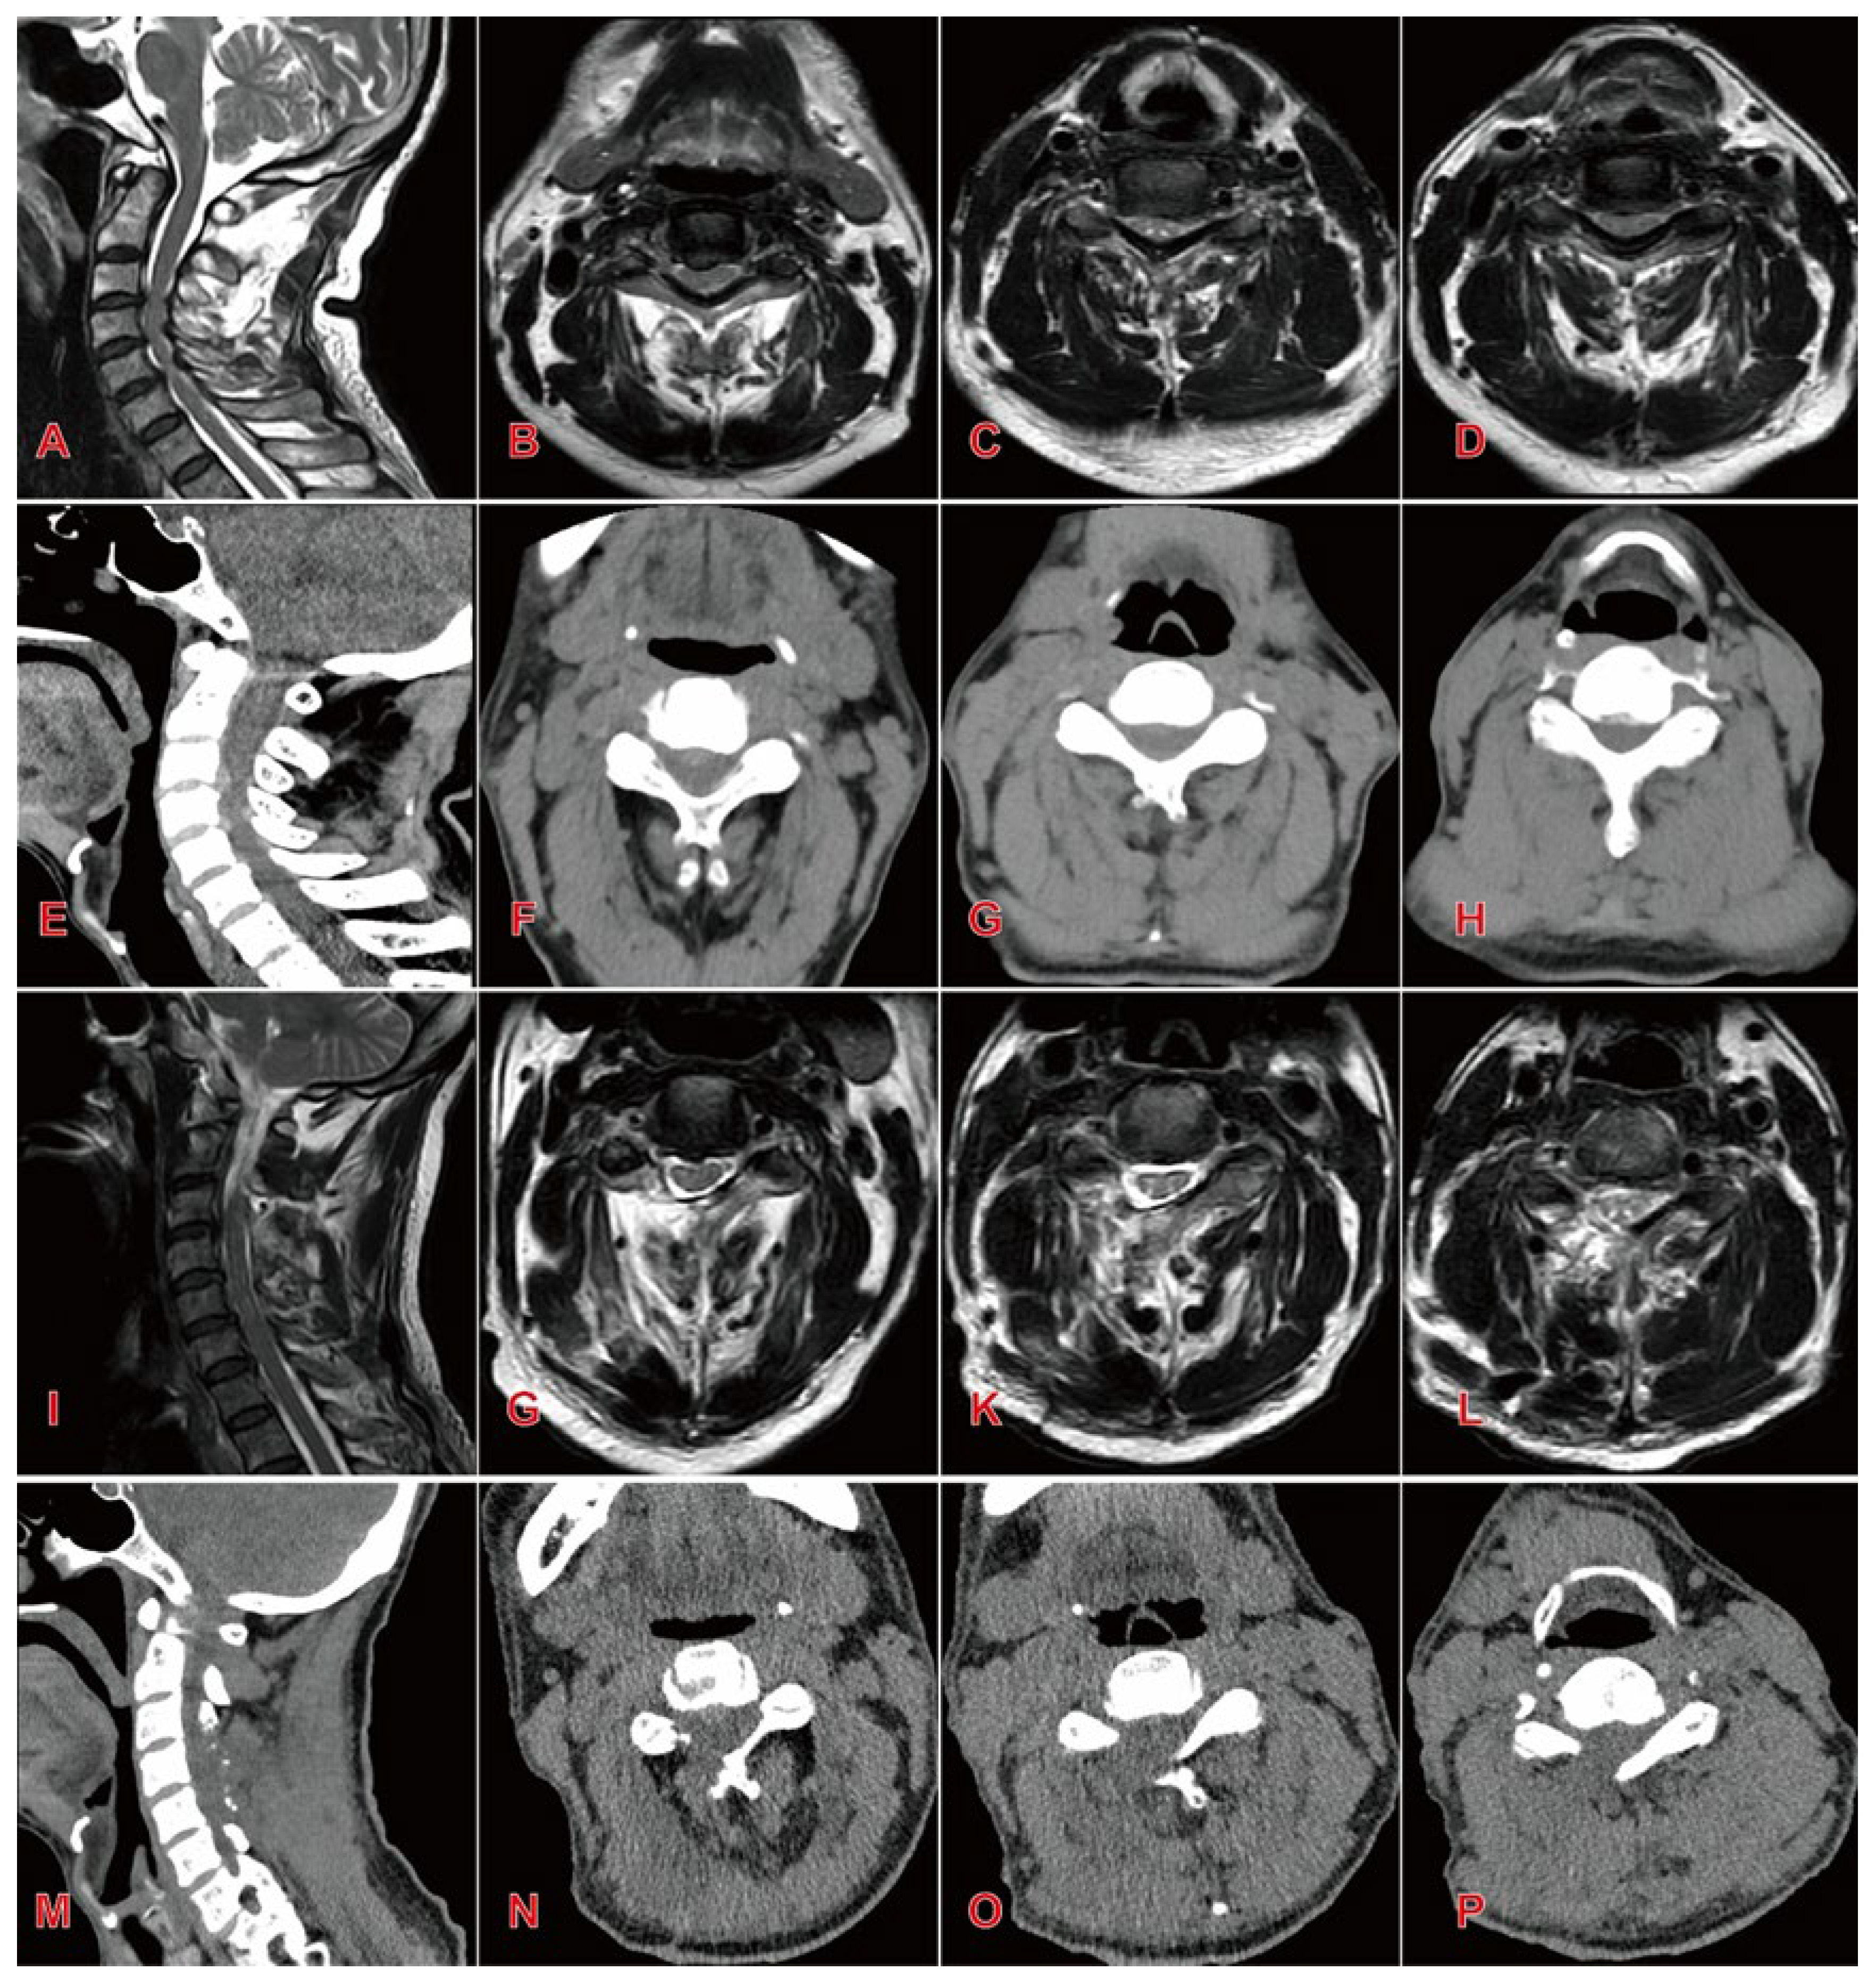

Objectives: To investigate the clinical effect and safety of large-channel endoscopic unilateral laminotomy decompression for the treatment of multilevel cervical canal stenosis. Methods: A retrospective study was conducted on 36 Cervical spinal stenosis patients who underwent surgical treatment between January 2020–December 2023.Patients were divided into two groups according to the surgical method: endoscopic group(n=16) and open group(n=20).Perioperative Basic parameters were record and Clinical efficacy were systematically assessed using validated metrics: Visual Analog Scale , Japanese Orthopaedic Association score and Neck Disability Index. Radiographical parameters(C2–C7 Cobb angle, T1 slope, pavlov ratio) are used to assess the decompression effect and stability of cervical spine. Results: The endoscopic group demonstrated significant advantages over the open group in operative time , incision length , blood loss, and hospitalization duration . Both groups showed significant postoperative improvements in VAS, JOA, and NDI scores compared to preoperative baselines (P<0.05). At 1 month postoperatively, the endoscopic group exhibited superior VAS scores to the open group (2.69 ± 0.79 vs. 4.4 ± 0.88, P<0.05). Radiographic outcomes at final follow-up revealed significantly better cervical Cobb angle (13.57 ± 2.29° vs. 16.34 ± 2.95°, P<0.05) and T1 slope (22.62 ± 1.51° vs. 25.24 ± 2.41°, P<0.05) in the endoscopic group. Conversely, the open group demonstrated greater postoperative spinal canal area and Pavlov ratio (P<0.05). Conclusions: The large-channel endoscopic unilateral laminotomy decompression demonstrates satisfactory short-term efficacy in treating multilevel Cervical Spinal Stenosis. This technique offers significant advantages including reduced surgical trauma, accelerated recovery, enhanced postoperative cervical stability and higher patient satisfaction.